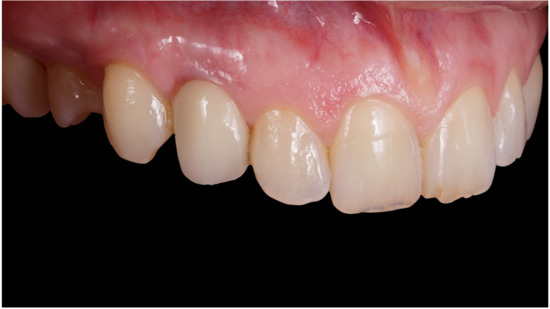

Figure 6.

Healing of soft tissues around the temporary crown.

Definitive crown after 1 year of follow-up, frontal view.

Figure 10.